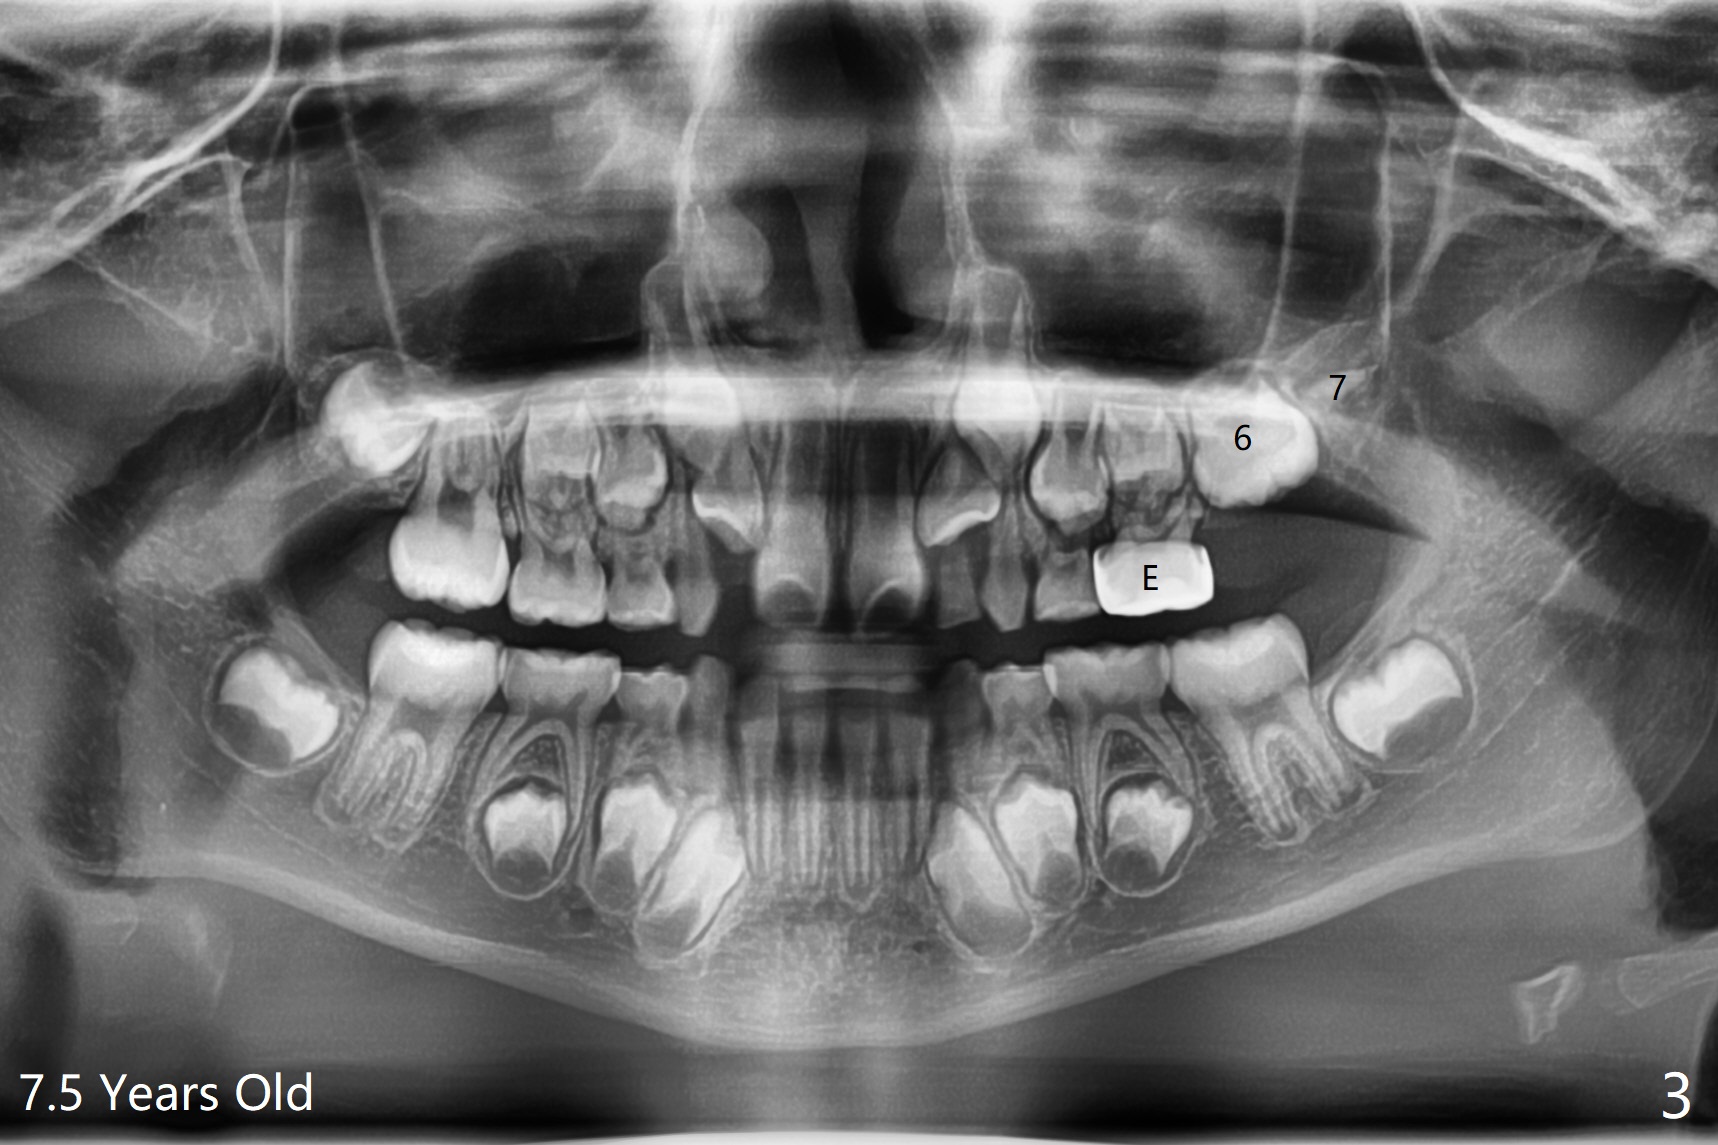

The upper left 1st permanent molar of a female remains unerupted between the age of 6 and 8 years old (Fig.1-4). The distal root of E is resorbed (Fig.3), which may be a reason of blockage. It appears that the upper left molars are underdeveloped, including 7. Or UL6 is congenitally missing? What is the treatment plan? Wait or surgery?

I have seen this before where a 6 looks like a 7! It behaves like a ‘9-year

molar’ in terms of root development and eruption! It is a variant.